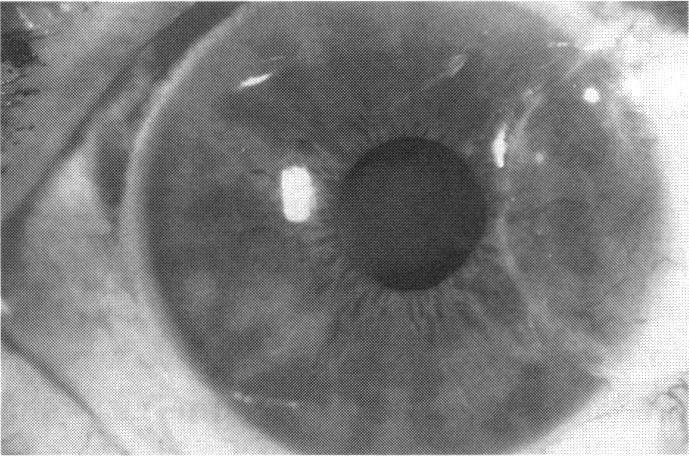

Human Subjects. Of the 19 human subjects included, 18 (20 procedures) underwent in vitro cultured corneal epithelial cell transplants using various carriers for the epithelial cells to determine the most efficacious approach. Sixteen patients (18 procedures on 17 eyes) received autologous transplants, and 2 patients (1 procedure each) received allogeneic sibling grafts. The presumed corneal epithelial stem cells from 1 patient did not grow in vitro. The carriers for the expanded corneal epithelial cells included corneal stroma, type 1 collagen (Vitrogen), soft contact lenses, collagen shields, and amniotic membrane for the autologous grafts and only amniotic membrane for the allogeneic sibling grafts. Histologic confirmation was reviewed on selected donor grafts. Amniotic membrane as carrier. Further studies were made to determine whether amniotic membrane might be the best carrier for the expanding corneal epithelial cells. Seventeen different combinations of tryspinization, sonication, scraping, and washing were studied to find the simplest, most effective method for removing the amniotic epithelium while still preserving the histologic appearance of the basement membrane of the amnion. Presumed corneal epithelial stem cells were harvested and expanded in vitro and applied to the amniotic membrane to create a composite graft. Thus, the composite graft consisted of the amniotic membrane from which the original epithelium had been removed without significant histologic damage to the basement membrane, and the expanded corneal epithelial stem cells, which had been applied to and had successfully adhered to the denuded amniotic membrane. Animal model. Twelve rabbits had the ocular surface of 1 eye damaged in a standard manner with direct removal of the presumed limbal stem cells, corneal epithelium, and related epithelium, followed by the application of n-heptanol for 60 seconds. After 6 weeks, all damaged eyes were epithelialized and vascularized. Two such treated eyes were harvested without further treatment, to be used for histologic study as damaged controls. The remaining 10 rabbits received composite grafts (consisting of amniotic membrane with expanded allogeneic rabbit corneal epithelial cell transplants) applied to the ocular surface in a standard manner followed by the application of a contact lens. At 16 days following transplantation, 5 of the rabbits were sacrificed and the corneal rims were removed for histologic study. At 28 days, the remaining rabbits were sacrificed and the previously damaged eyes were harvested for histologic and immunohistochemical study.

RESULTS

Human subjects. Of the 19 total patients admitted to the study, the presumed corneal epithelial stem cells of 1 patient did not grow in vitro. Of the remaining 18 patients (20 procedures, 19 eyes), 3 patients had unsuccessful results (3 autologous procedures), 1 patient had a partially successful procedure (allogeneic procedure), and 1 patient had a procedure with an undetermined result at present (allogeneic procedure). One unsuccessful patient had entropion/trichiasis and mechanically removed the graft and eventually went into phthisis. The other 2 unsuccessful patients suffered presumed loss of autologous donor epithelium and recurrence of the ocular surface disease (pterygium). The partially successful patient receiving an allogeneic transplant had infectious keratitis delay of his re-epithelialization; he has only minimal visual improvement but has re-epithelialized. The patient receiving the second allogeneic graft lost his donor epithelium at day 4. Additional donor epithelium was reapplied, but the result is undetermined at present. Amniotic membrane as carrier. The in vitro preparation of the amniotic membrane with corneal epithelial stem cell graft overlay was successful. Histology documented removal of the amniotic epithelium and reapplication of corneal epithelial cells. Animal model. The 2 rabbits that had no reparative surgery following standard ocular surface injury had histology and immunopathology consistent with incomplete corneal epithelial stem cell failure with vascularization and scarring of the ocular surface. Light microscopy and immunohistologic staining with AE5 confirmed the conjunctival phenotype of the ocular surface repair but also documented the incomplete model. The allogeneic stern cell transplants had varying results. One rabbit had a suppurative infection and lost the graft. Reparative surgery failed in 2 of the rabbits, failed partially in 3 of the rabbits, was partially successful in 3 others, and was successful in 1 rabbit at 28 days. Histologic and immunopathologic study documented successful growth of corneal epithelium onto the recipient surface.

人类受试者。纳入的19名人类受试者中,18名(20例手术)使用上皮细胞的各种载体进行了体外培养角膜上皮细胞移植,以确定最有效的方法。16例患者(17只眼的18例手术)接受了自体移植,2例患者(各1例手术)接受了异体同胞移植。1例患者的假定角膜上皮干细胞在体外未生长。扩增角膜上皮细胞的载体包括角膜基质、1型胶原蛋白(Vitrogen)、软性隐形眼镜、胶原盾和羊膜用于自体移植,而异体同胞移植仅使用羊膜。对选定的供体移植物进行了组织学确认。羊膜作为载体。进一步研究以确定羊膜是否可能是扩增角膜上皮细胞的最佳载体。研究了17种不同的胰蛋白酶消化、超声处理、刮除和冲洗组合,以找到去除羊膜上皮同时仍保留羊膜基底膜组织学外观的最简单、最有效的方法。采集假定的角膜上皮干细胞并在体外扩增,然后应用于羊膜以制备复合移植物。因此,复合移植物由已去除原始上皮且基底膜无明显组织学损伤的羊膜以及已应用并成功粘附于裸露羊膜的扩增角膜上皮干细胞组成。动物模型。12只兔子的1只眼的眼表以标准方式受损,直接去除假定的角膜缘干细胞、角膜上皮和相关上皮,然后应用正庚醇60秒。6周后,所有受损眼均上皮化且血管化。2只经如此处理的眼未进一步治疗即被采集,用作组织学研究的受损对照。其余10只兔子接受以标准方式应用于眼表的复合移植物(由带有扩增异体兔角膜上皮细胞移植的羊膜组成),随后应用隐形眼镜。移植后16天,处死5只兔子,取出角膜缘进行组织学研究。28天时,处死其余兔子,取出先前受损的眼进行组织学和免疫组织化学研究。

结果

人类受试者。纳入研究的19例患者中,1例患者的假定角膜上皮干细胞在体外未生长。其余18例患者(20例手术,19只眼)中,3例患者手术结果不佳(3例自体手术),1例患者手术部分成功(异体手术),1例患者目前手术结果未确定(异体手术)。1例手术失败的患者患有睑内翻/倒睫,机械性移除了移植物,最终眼球萎缩。另外2例手术失败的患者假定自体供体上皮丢失且眼表疾病(翼状胬肉)复发。接受异体移植的部分成功患者发生感染性角膜炎,上皮化延迟;他的视力仅略有改善,但已重新上皮化。接受第二次异体移植的患者在第4天失去了供体上皮。重新应用了额外的供体上皮,但目前结果未确定。羊膜作为载体。羊膜与角膜上皮干细胞移植物覆盖物的体外制备成功。组织学证实羊膜上皮已去除且角膜上皮细胞已重新应用。动物模型。2只在标准眼表损伤后未进行修复手术的兔子的组织学和免疫病理学结果与角膜上皮干细胞不完全衰竭一致,伴有眼表血管化和瘢痕形成。光学显微镜检查和用AE5进行的免疫组织化学染色证实了眼表修复的结膜表型,但也记录了不完全模型。异体干细胞移植结果各异。1只兔子发生化脓性感染,移植物丢失。2只兔子的修复手术失败,3只兔子部分失败,另外3只部分成功,1只兔子在28天时成功。组织学和免疫病理学研究记录了角膜上皮在受体表面的成功生长。